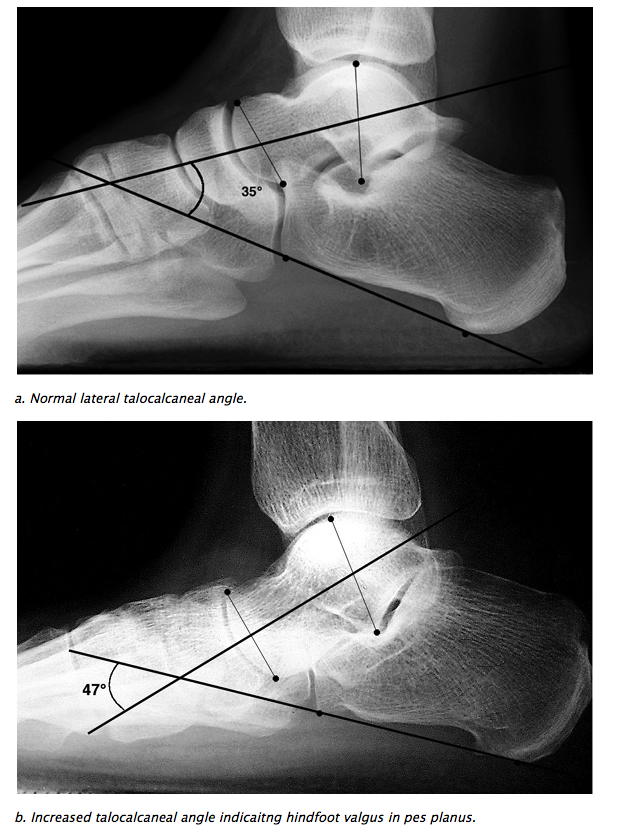

HINDFOOT VALGUS

• Lateral: Talo-calcaneal angle